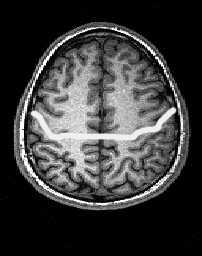

МРТ головного мозга. Аксиальный срез. Центральная борозда (стрелки).

МРТ головного мозга. Аксиальный срез на уровне крыши боковых желудочков. Центральная борозда (стрелки).